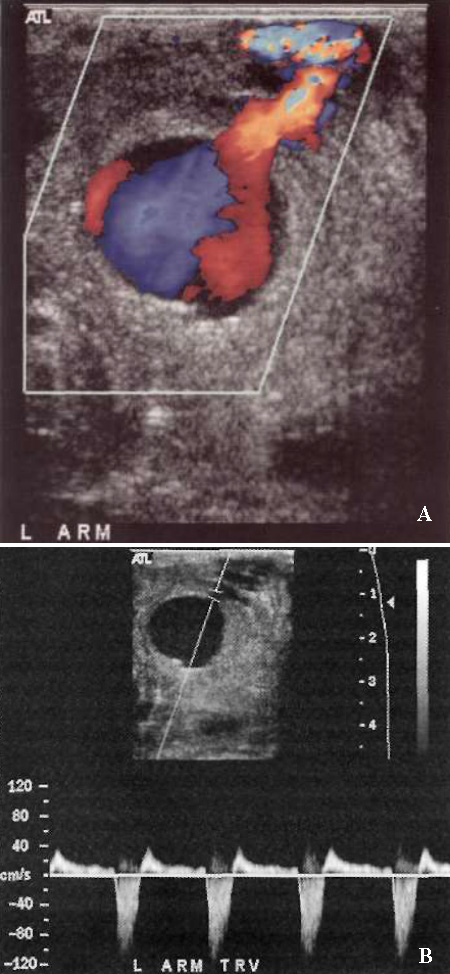

Наиболее частой локализацией ложной аневризмы является общая бедренная артерия, поверхностная бедренная артерия, подколенная, лучевая, почечная и селезеночная артерии. Кроме этого, ложные аневризмы могут формироваться вокруг искусственных сосудов – шунтов (фото 2).

УЗИ: Ложная аневризма артериовенозной диализной фистулы

Фото 2. Ложная аневризма артериовенозной диализной фистулы. А – цветовая допплерограмма демонстрирует ложную аневризму, которая исходит из артериовенозной диализной фистулы. В – спектральная допплерограмма демонстрирует кровоток внутрь и наружу из аневризмы характерной двухфазной формы с полным обратным током в диастолу